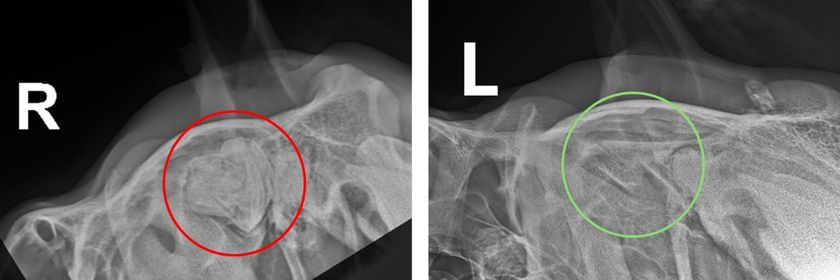

Figure 1 – The red circle highlights abnormal tooth structures in the skull near the ear base on the right side. The green circle highlights normal anatomy on the left side of the head.

King was admitted to our clinic for further investigation, including radiographs and an ultrasound of his head (figure 1). These confirmed our suspicions, revealing a large tooth-like structure lurking deep within his skull – definitely not where you would be expecting to find a tooth! This misplaced tooth leads to a discharge that tracks through the tissues and eventually drains at the base of the ear.